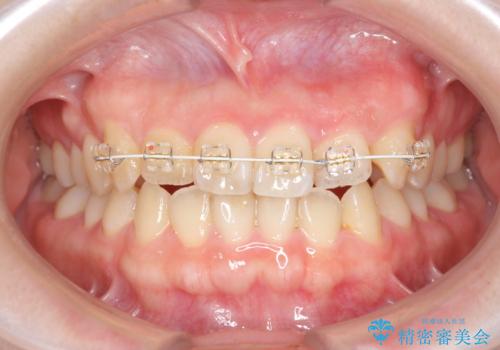

- ねじれの目立つ前歯を改善したいと、矯正治療を希望され来院されました。

マススピース矯正を始める前に、部分ワイヤー矯正を行うことで治療の短期間化・良好な仕上がりを達成することができました。

- 1年3ヶ月